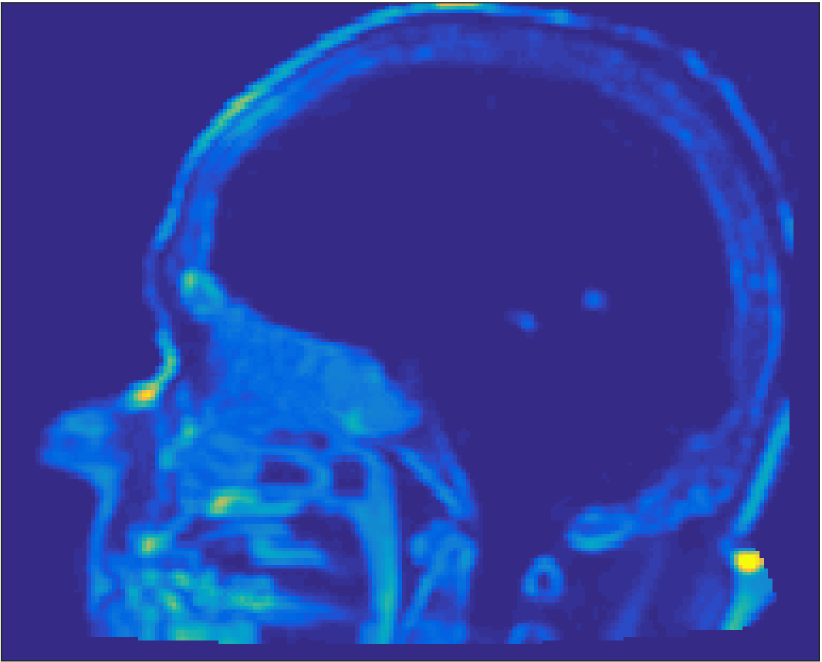

All MR images were acquired with a 1.5 T Siemens Espree scanner. The UTE images were reconstructed to 192×192×192192192192192\times 192\times 192 voxel bitmapped images with an isotropic resolution and a voxel size of 1.33 mm. The UTE sequences sampled the k-space radially with 30 000 radial spokes. CT images were acquired with a tube voltage of between 120 kV and 130 kV on either a GE Lightspeed Plus, Siemens Emotion 6 or GE Discovery 690. The in-plane pixel size varied between 0.48 mm to 1.36 mm and the slice thickness between 2.5 mm and 3.75 mm. Images of the same patient were co-registered and resampled to achieve voxel-wise correspondence between all five modes. A binary mask excluding most of the air surrounding the head was computed from the images and used to remove unnecessary data. Furthermore, to reduce the execution time of the parameter estimation phase, only 11 slices in the middle of the head of each patient was used during the parameter estimation phase, but all slices were used during the prediction phase (s-CT generation). Additional details concerning the data can be found in Johansson et al. [16]. Data from one slice of a patient is shown in Figure 3.

Refer to caption

(a) Binary mask

(b) CT

(c) First echo, 10superscript1010^{\circ}

(d) Second echo, 10superscript1010^{\circ}

(e) First echo, 30superscript3030^{\circ}

(f) Second echo, 30superscript3030^{\circ}

Figure 3: Binary data mask (panel a), CT image (panel b), The four MRI UTE sequences (panels c-f).